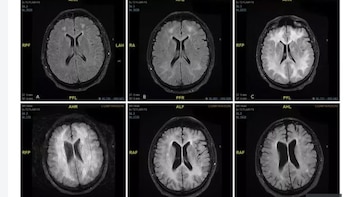

En 2019 se realizó un estudio con imágenes cerebrales de resonancia magnética de un consumidor habitual de cocaína. Así se reveló el daño que la droga puede causar con el tiempo. El paciente no identificado fue diagnosticado con una condición rara llamada leucoencefalopatía tóxica inducida por cocaína después de abusar regularmente durante años.

Los estudios fueron efectuados en el hospital de Msida, de Malta. Según los profesionales que atendieron al paciente, se trata de un hombre de 45 años que estaba confundido y se comportaba de manera extraña, antes de que los médicos se dieran cuenta de que padecía leucoencefalopatía tóxica inducida por cocaína.

El doctor Ylenia Abdilla, que trató al hombre no identificado, explicó: “Es un trastorno raro que puede causar una discapacidad significativa. Este estudio de caso está destinado a aumentar la conciencia de esta condición”. Y agregó: “El pronóstico generalmente es malo y puede ser rápidamente mortal; sin embargo, algunos casos raros se recuperan por completo, como se ve en este informe de caso”.